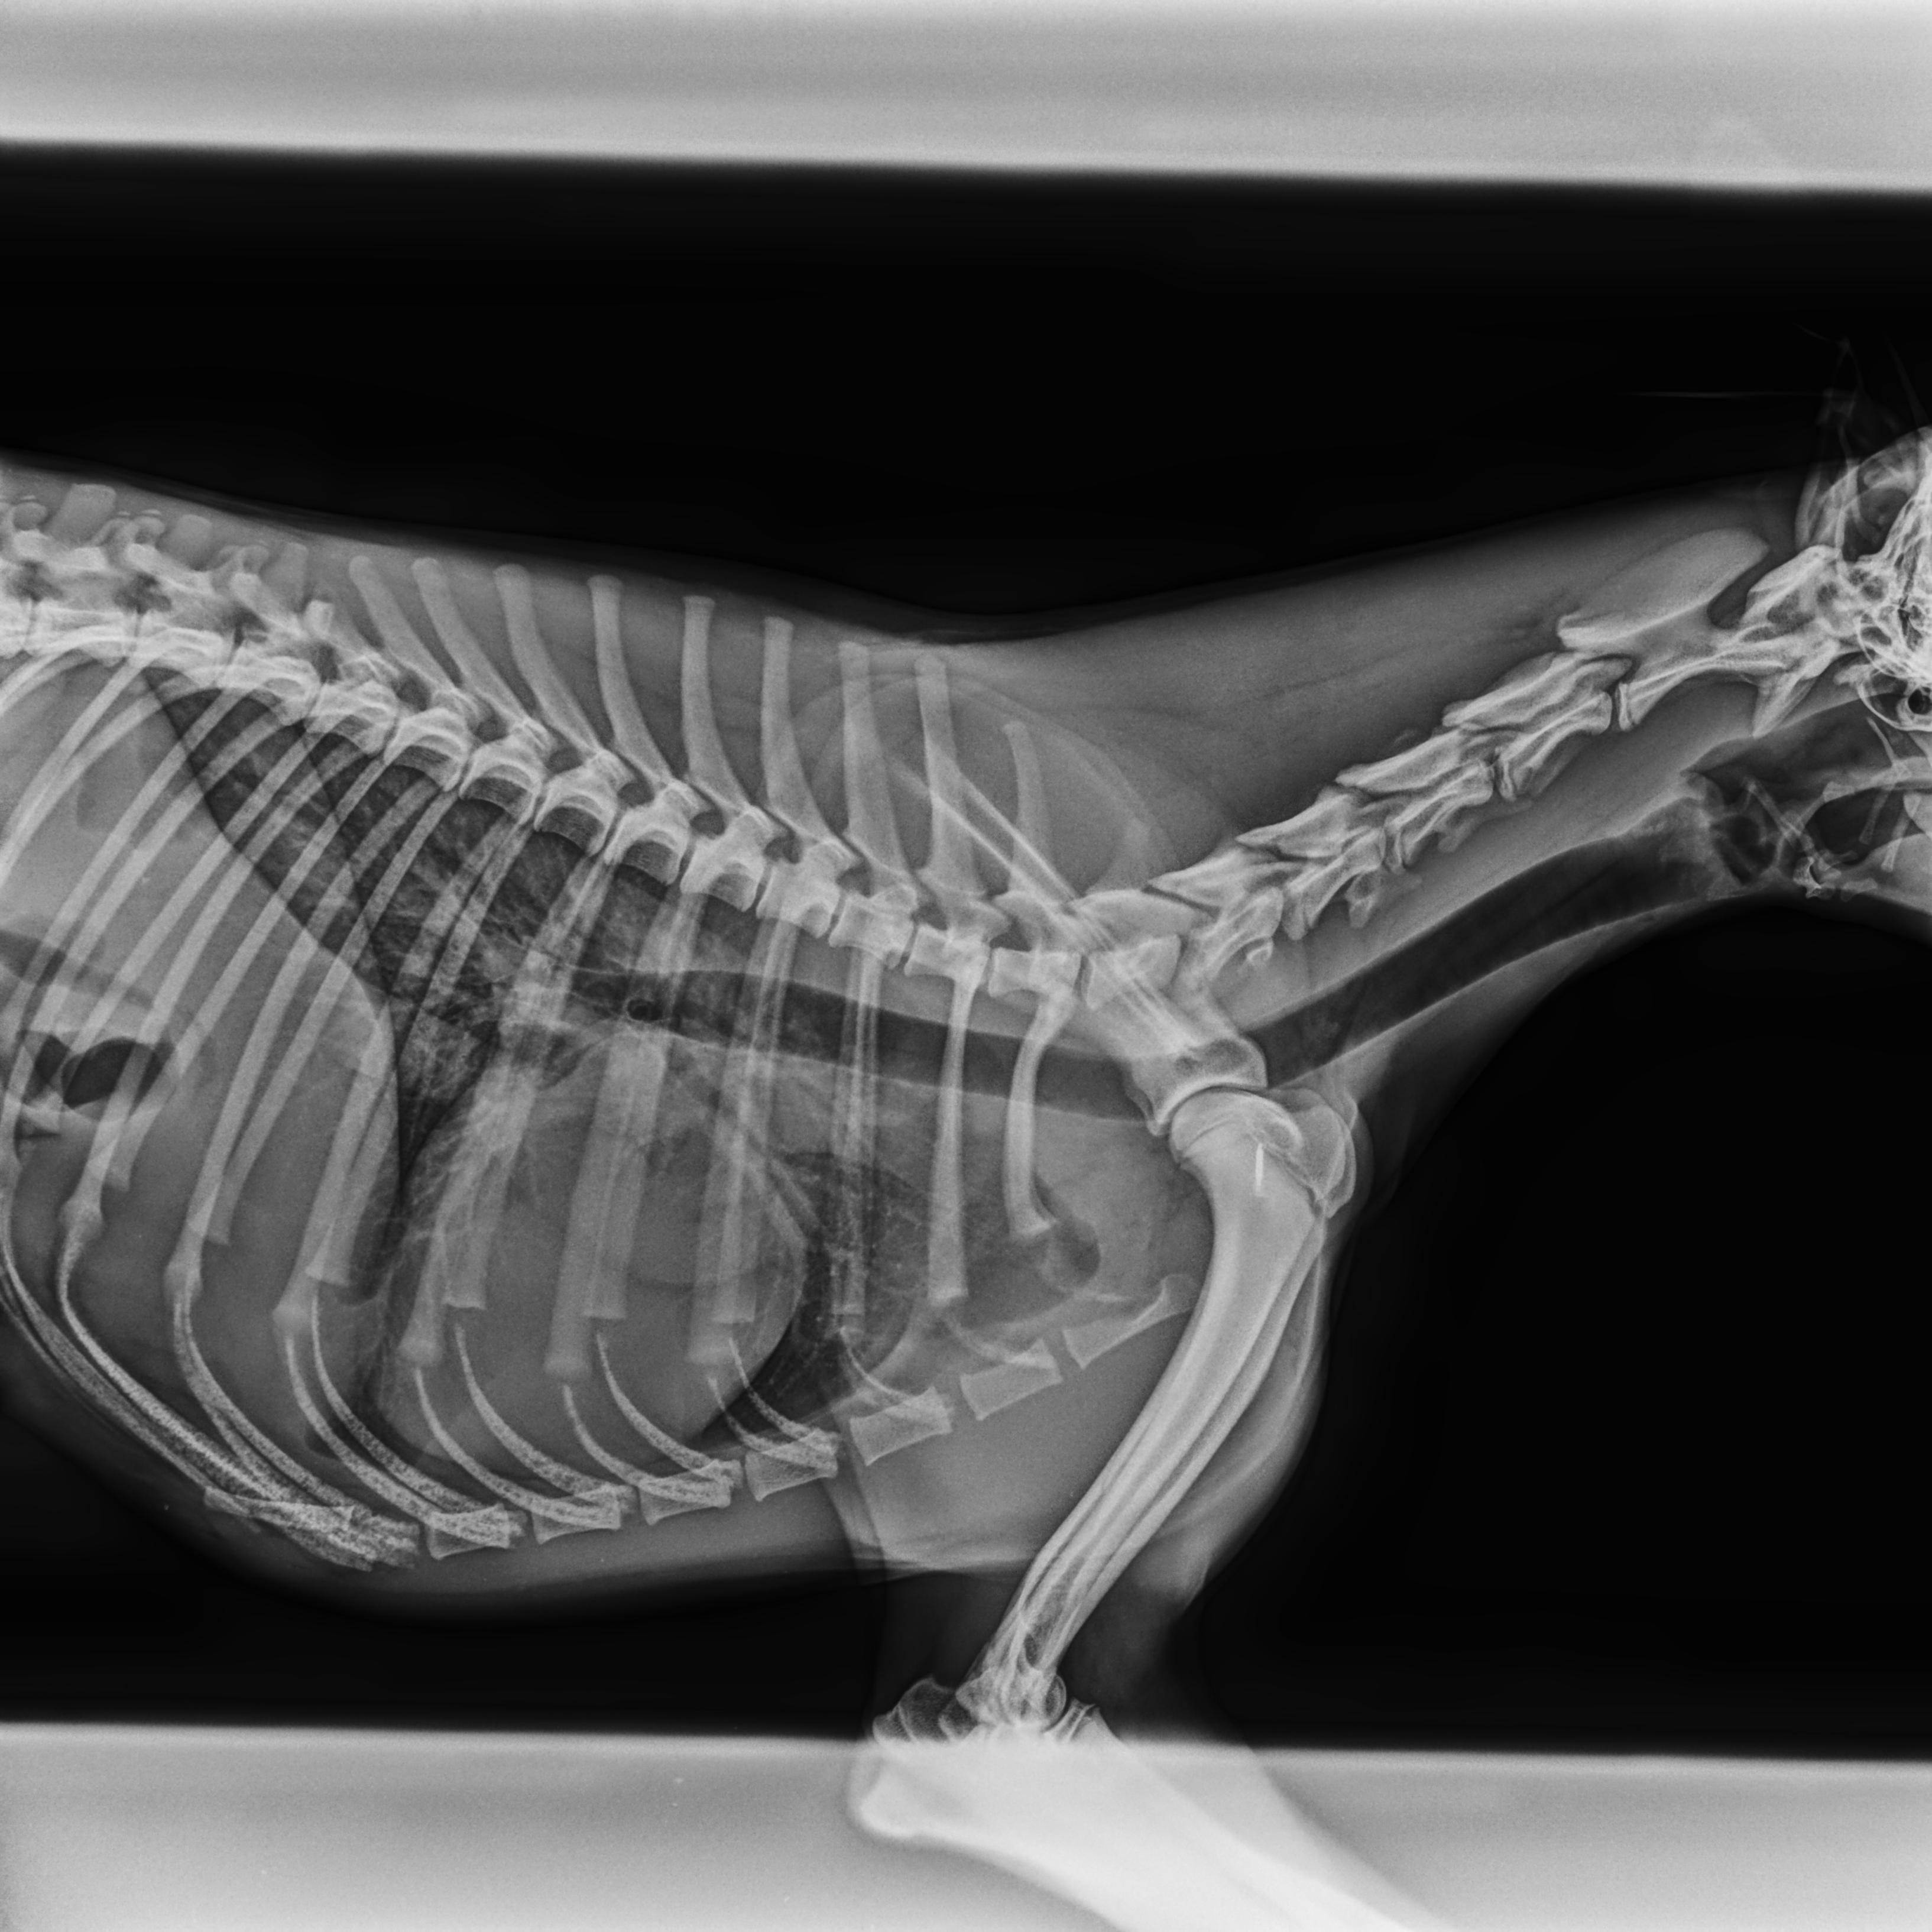

Cushingův syndrom, taktéž nazývaný Hyperadrenokorticismus, patří v současnosti spolu s diabetes mellitus mezi nejčastěji se vyskytující endokrinologická onemocnění psů. Způsobuje ho nadbytek glukokortikoidů, jako Cushingův syndrom pak označujeme soubor příznaků, které onemocnění doprovázejí.